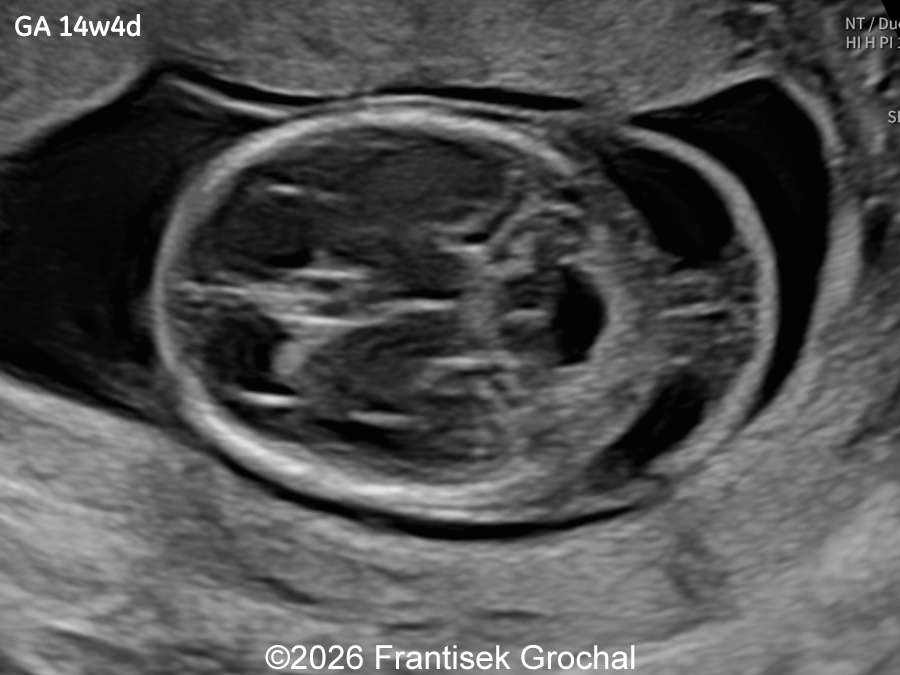

A 30-year-old primigravida presented to our outpatient clinic for ultrasound examinations at 14 and subsequently at 19 weeks of gestation. In a male fetus, the following findings were identified:

Ultrasound examination at 14 weeks demonstrated marked nuchal edema, nasal bone hypoplasia, and a suspected ventricular septal defect.